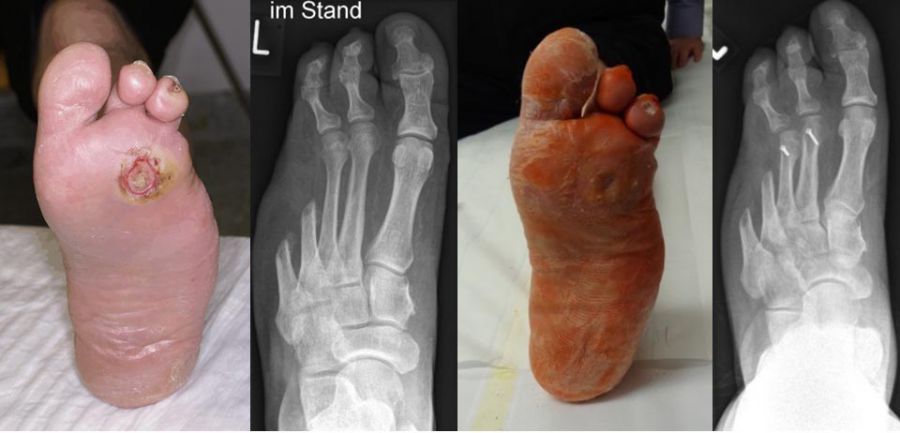

- Operative Behandlung von Druckstellen durch Hallux valgus

Aufgrund einer Fehlstellung der Großzehe nach außen (Hallux valgus) kann es zu Druckstellen bzw. Hautläsionen zwischen der 1. und 2. Zehe sowie kommen. Gefährdet ist auch die Haut auf der Innenseite des Fußes über dem Großzehengrundgelenk. Sollten hier konservative Therapiemaßnahmen (Polsterung/Schuhzurichtung) versagen, ist eine operative Korrektur des Hallux valgus anzuraten. - Operative Behandlung von Druckstellen durch Hammerzehen

Bei Hallerzehenfehlstellung kann es zu Druckstellen bzw. Hautschäden an der Zehenspitze oder über dem Zehenmittelgelenk kommen.Sollten hier konservative Therapiemaßnahmen (Polsterung/Schuhzurichtung) versagen, ist eine operative Korrektur der Hammerzehe sinnvoll, bevor offene Stellen entstehen, die dann zu Eintrittspforten für Keime werden.

Zum Lesen der Bildbeschreibung und Vollansicht bitte Bild anklicken. Fotos: Alexander Mehlhorn

- Operative Behandlung von Druckstellen durch Überlänge eines oder mehrerer Mittelfußknochen

Anlagebedingt oder nach Amputationen kann es zu einer Überlänge von einem Mittelfußknochen relativ zu den anderen Mittelfußknochen kommen. Dies führt zu einer erhöhten Druckbelastung an der Fußsohle. Zunächst treten Schwielen auf, im Verlauf kommt es dann zu offenen Stellen und einem Ulkus. Sollten hier konservative Therapiemaßnahmen (Polsterung/Schuhzurichtung) versagen, ist eine operative Verkürzung oder Anhebung des entsprechenden Mittelfußknochens sinnvoll, um den Druck zu reduzieren. Auch dies ist heute meist minimalinvasiv in Schlüssellochtechnik möglich.